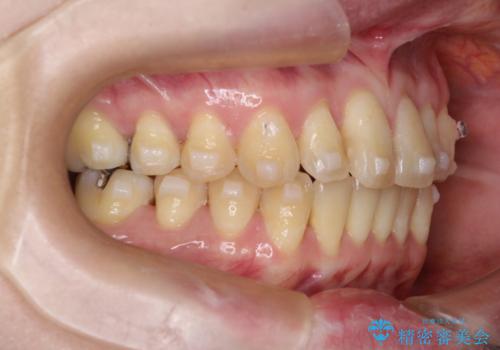

【インビザライン】前歯の捻れとオープンバイト

- 上の前歯の捻れと、前歯で物が噛めないことを主訴に来院されました。

前歯の翼状捻転とオープンバイト傾向だったため、インビザラインにて矯正を行いました。右下の奥歯は保存不可だったため、抜歯を行いインプラントにて修復を行なっています。

翼状捻転はインビザラインでは苦手とする動きですが、ここまで綺麗に治すことができました。